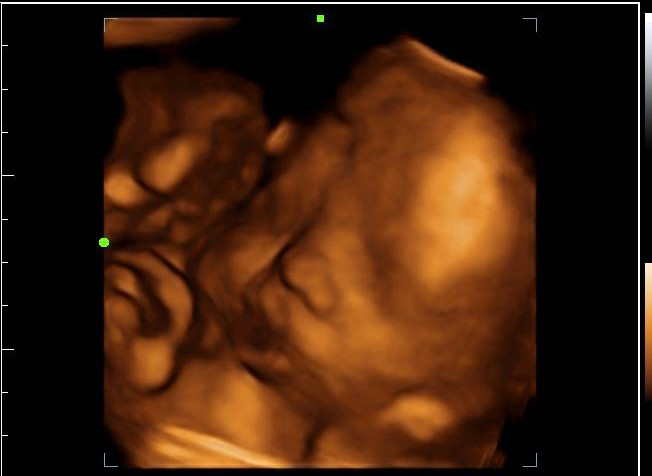

My business is a mobile ultrasound company. I come to your home, bring everything I need and do your Ultrasound while you lay on your couch surrounded by friends and family. I have had so much fun getting to know my families and doing all the fun parts of ultrasound. I do early pregnancy, gender reveals, baby showers, 2D and 3D/4D. Getting started wasn’t easy, I built my website, I got an equipment loan, I got some quotes, purchased my equipment and started advertising my services with social media.